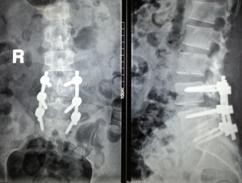

9.脊柱手术:适用于于腰椎间盘突出症,腰椎管狭窄症,脊柱骨折等各种脊柱病变。

L4/5、L5/S1巨大椎间盘突出